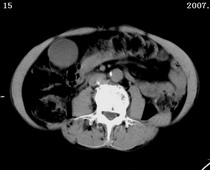

以下是引用zjzjr在2007-9-15 22:24:00的发言:[br]胰头钩突略饱满,肝内外胆管略扩张,胆囊积水.建议增强扫描.

以下是引用代课学生在2007-9-16 10:20:00的发言:[br]胆总管中段以上胆管均示扩张,考虑胆总管下段/胰头部病变,建议增强或micp检查。